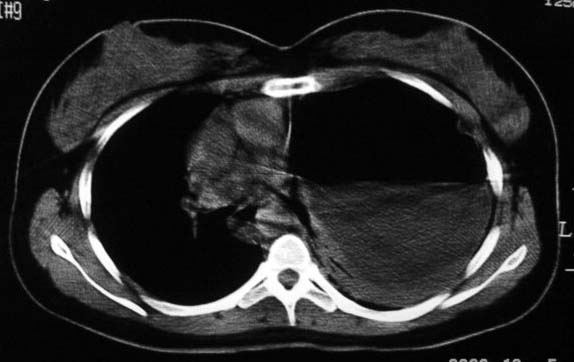

标题: CT5517:女性、24岁,反复胸痛、气促不能平卧半月。 [打印本页]

标题: CT5517:女性、24岁,反复胸痛、气促不能平卧半月。

左肺可见二个含气或液气的囊状影,左肺段支气管、左肺动脉显示不清,纵隔右移,考虑:左肺支气管肺囊肿,左肺发育不良,纵隔疝。

左侧气液腔与胃腔影相连,考虑膈疝。钡餐检查有助于诊断。

我看这是膈疝,在纵隔窗第六\\七幅图像上可见胃粘膜影,再者可见两个腔影,这在液气胸是不会有的.

支持膈疝,纵隔窗内可见消化道的内容物。

“反复胸痛、气促不能平卧半月”。+影像学表现=膈疝